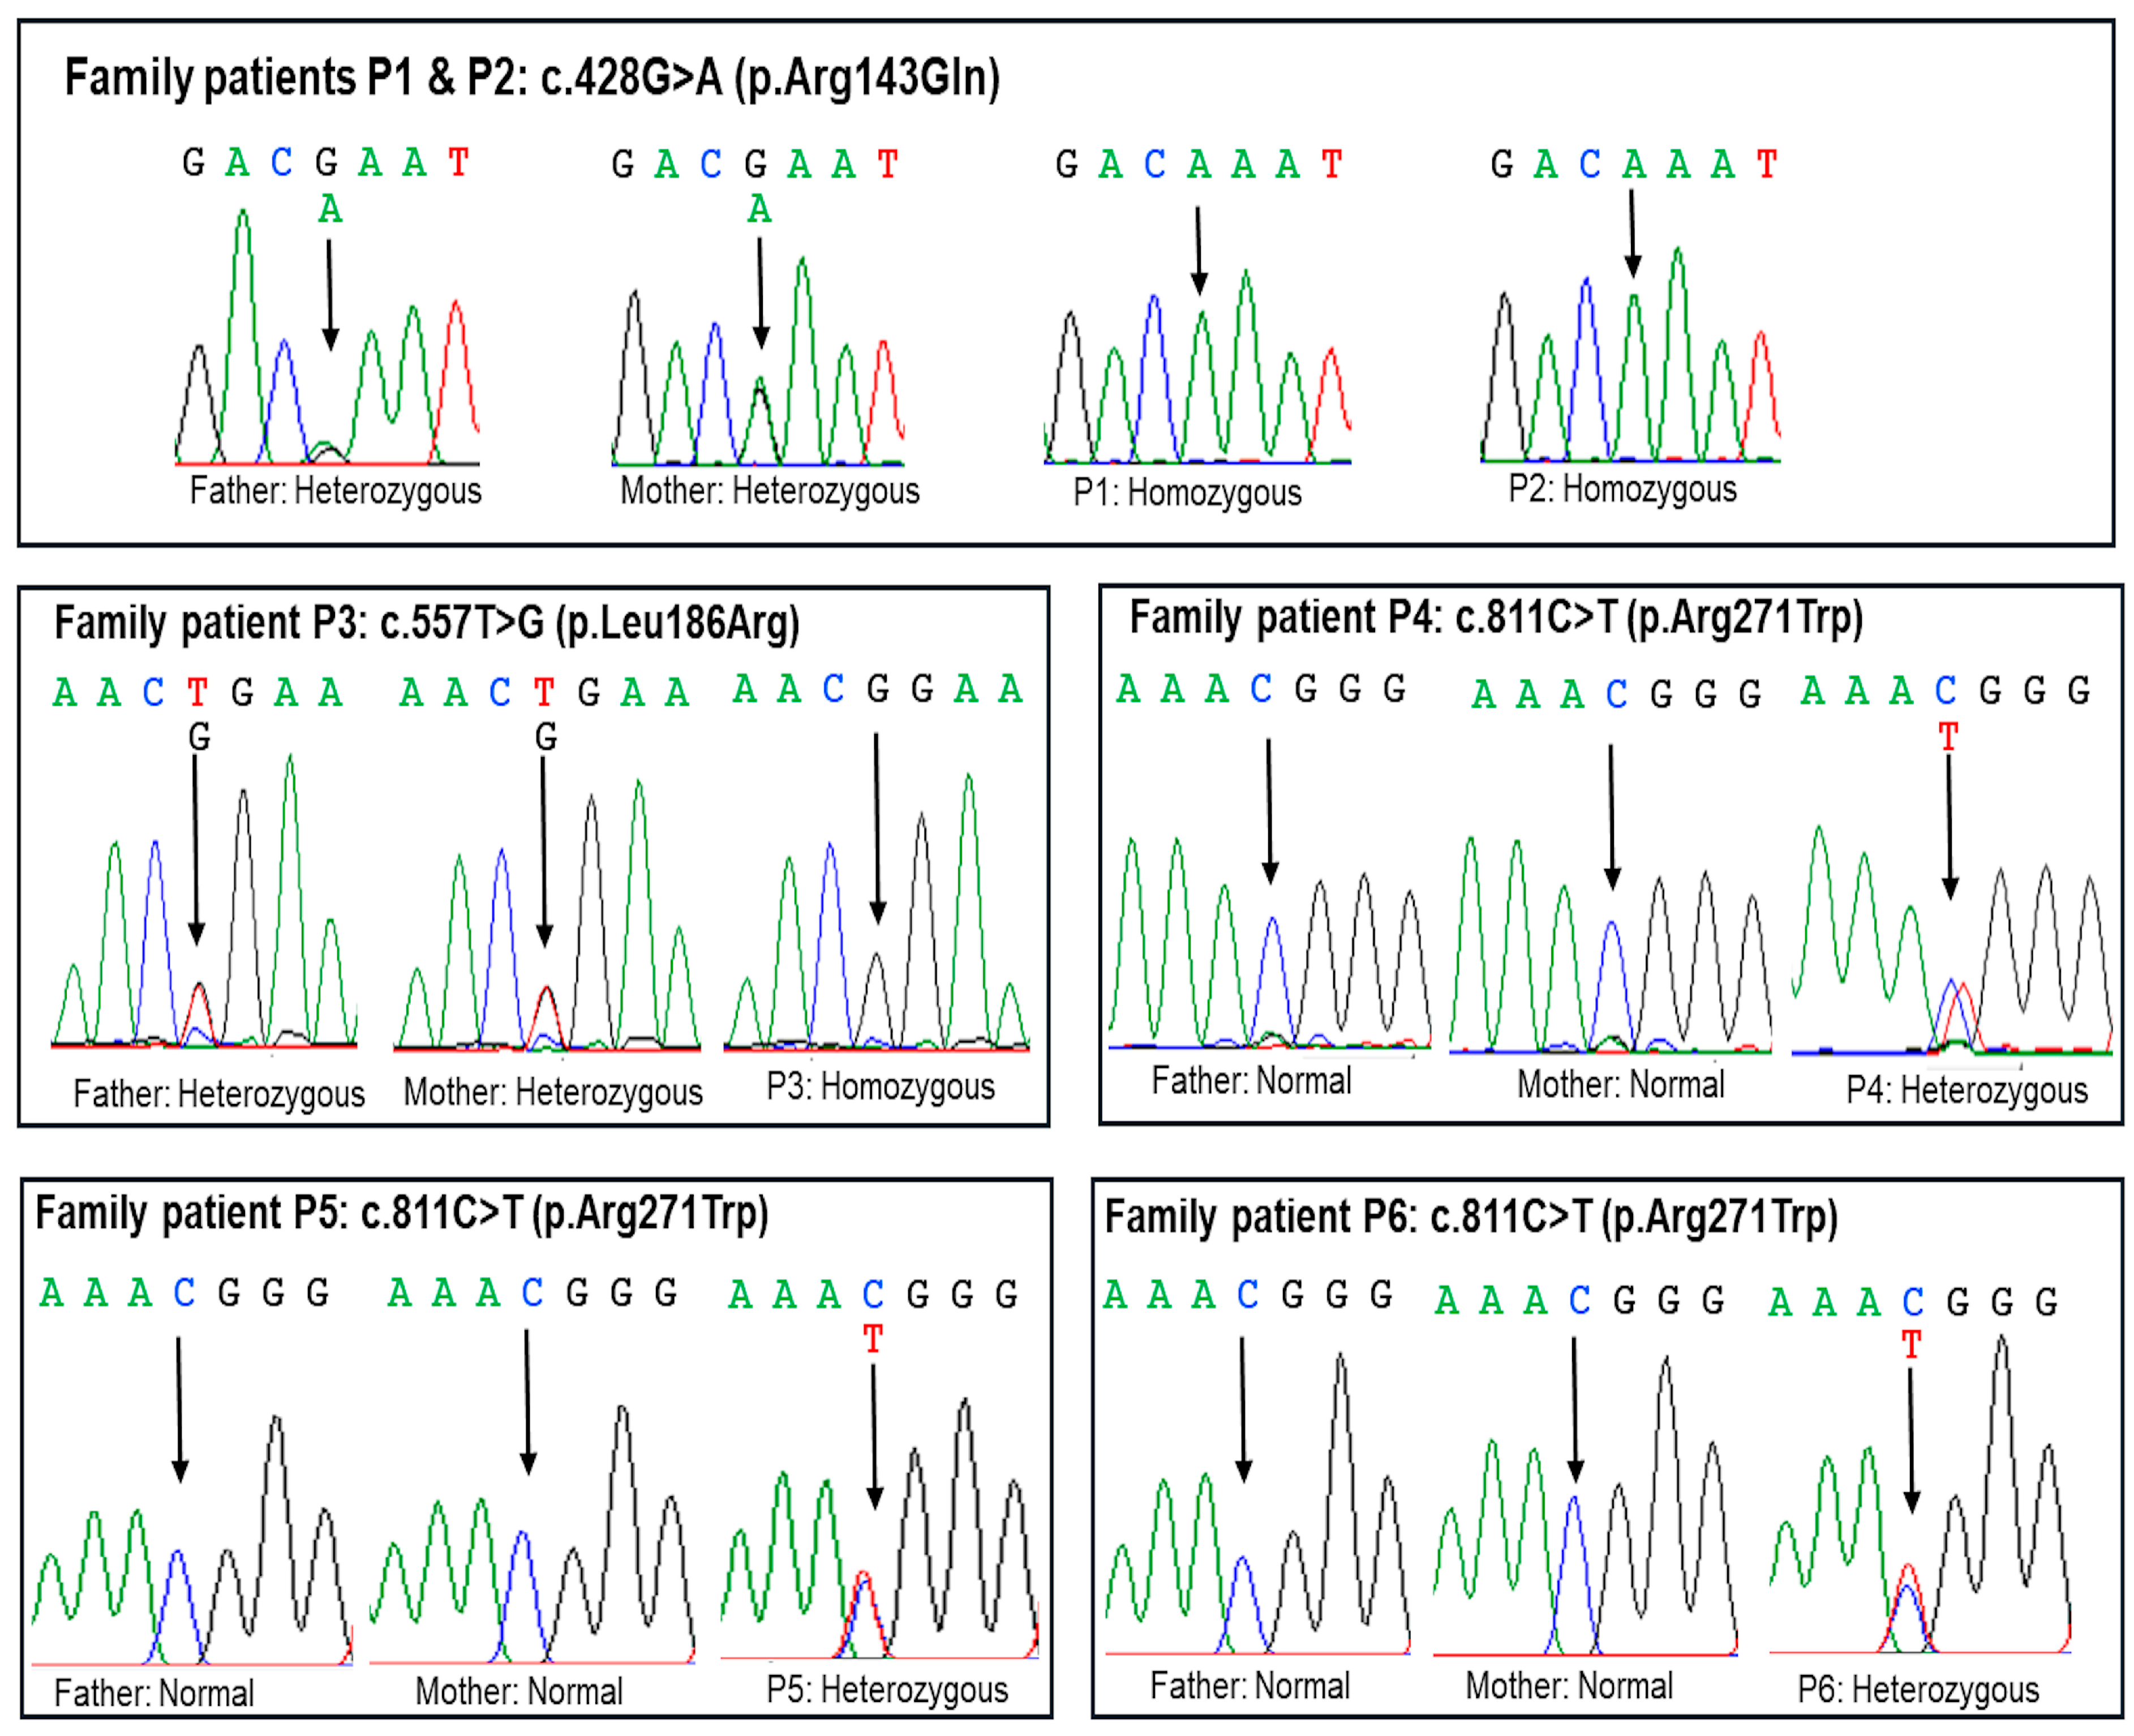

2.2. Molecular Findings

| Patient | P1 and P2 | P3 | P4, P5, and P6 |

|---|---|---|---|

| Gene | POU1F1 | POU1F1 | POU1F1 |

| Locus | chr3:87313449C>T | chr3:87311268A>C | chr3:87309109G>A |

| Exon | 3 | 4 | 6 |

| c.DNA change (NM_000306.4) | c.428G>A | c.557T>G | c.811C>T |

| Amino acid change | p.(Arg143Gln) | p.(Leu186Arg) | p.(Arg271Trp) |

| Status in the patient | Homozygous | Homozygous | Heterozygous |

| Segregation | Paternal and maternal | Paternal and maternal | De novo |

| Inheritance pattern | Autosomal recessive | Autosomal recessive | Autosomal dominant |

| CADD (Phred score) | Damaging (33) | Damaging (31) | Damaging (28.7) |

| SIFT prediction | Deleterious | Deleterious | Deleterious |

| PolyPhen_2 | Probably damaging | Probably damaging | Probably damaging |

| Mutation Taster | Deleterious | Deleterious | Deleterious |

| Minor allele frequency | 0.000004–0.000008 | 0 | 0 |

| dbSNP154 | rs104893759 | - | rs104893755 |

| ClinVar | 13606 Pathogenic | - | 13603 Pathogenic |

| LOVD v3.0 | 0000886010 | - | - |

| GnomAD v2.1.1 | 1 Heterozygous | 0 | 0 |

| Pathogenicity (ACMG 2015) | Likely pathogenic PM2, PM3, PP3, PP4 | Likely pathogenic PM2, PM3, PP3, PP4 | Pathogenic PS2, PM1, PM2, PP3, PP4 |